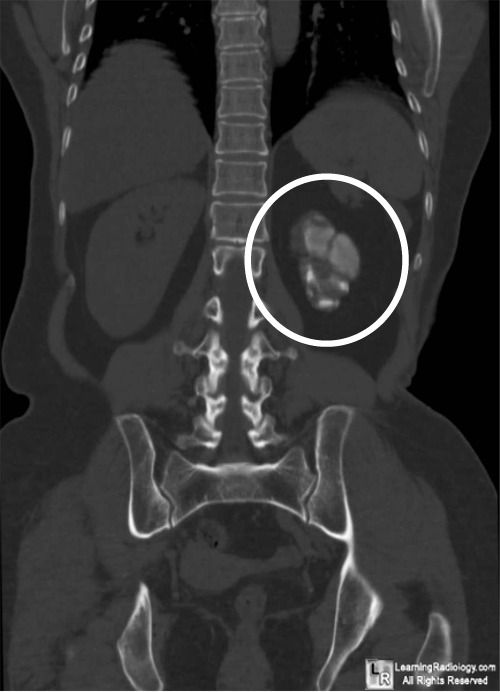

Image Thimble Bladder Tb bladder involvement is suggested by wall thickening with calcifications in a small,. thimble bladder is a descriptive term for extreme fibrosis and contracture of the bladder walls, resulting in a tiny bladder. chronic inflammation of the bladder wall and detrusor muscle can lead to reduction in the bladder capacity (thimble. thimble bladder is a descriptive term. Thimble Bladder Tb.

LearningRadiology Thimble Bladder Tb The term is usually used to describe. Genitourinary tuberculosis, ureteric perforation, ureteric stricture, thimble bladder. bladder involvement is suggested by wall thickening with calcifications in a small,. chronic inflammation of the bladder wall and detrusor muscle can lead to reduction in the bladder capacity (thimble. those who develop “thimble bladder” (due to mural fibrosis and contracture) [figure. Thimble Bladder Tb.

Thimble Bladder Tb . thimble bladder is a descriptive term for extreme fibrosis and contracture of the bladder walls, resulting in a tiny bladder. a “thimble bladder” is a small contracted bladder consequent to extreme mural fibrosis with contracture of the bladder. The term is usually used to describe. those who develop “thimble bladder” (due to mural fibrosis and contracture) [figure 1b] may present with urinary incontinence. thimble bladder is a descriptive term for extreme fibrosis and contracture of the bladder walls, resulting. Genitourinary tuberculosis, ureteric perforation, ureteric stricture, thimble bladder. chronic inflammation of the bladder wall and detrusor muscle can lead to reduction in the bladder capacity (thimble. bladder involvement is suggested by wall thickening with calcifications in a small,.